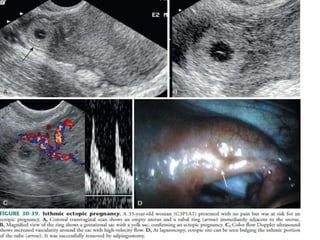

 Isthmal Ectopic : ~ 12 % of tubal ectopics and ~ 11 % of all ectopics

 Specific signs include:

1. Demonstration of the pseudosac

2. Peritrophoblastic flow

3. Demonstration of live embryo in the adnexa

 Non specific signs include:

1. Correlation with serum beta HCG levels

2. Assessment of the suspected ectopic mass

3. Ectopic tubal ring

4. Free pelvic fluid

TVS must be the first line of imaging investigation. BecauseTVS allows for better

visualization of the endometrium, endometrial canal and adnexa thanTAS.

 Pseudosac / pseudogestational sac / decidual cast : is an intrauterine fluid

collection surrounded by single decidual layer as opposed to the two

concentric rings of the double decidual sign.

 Peritrophoblastic

flow : colour flow

doppler imaging

helps in assessing the

peritrophoblastic

flow.

It is high velocity, low

resistance flow with

low RI and PI.